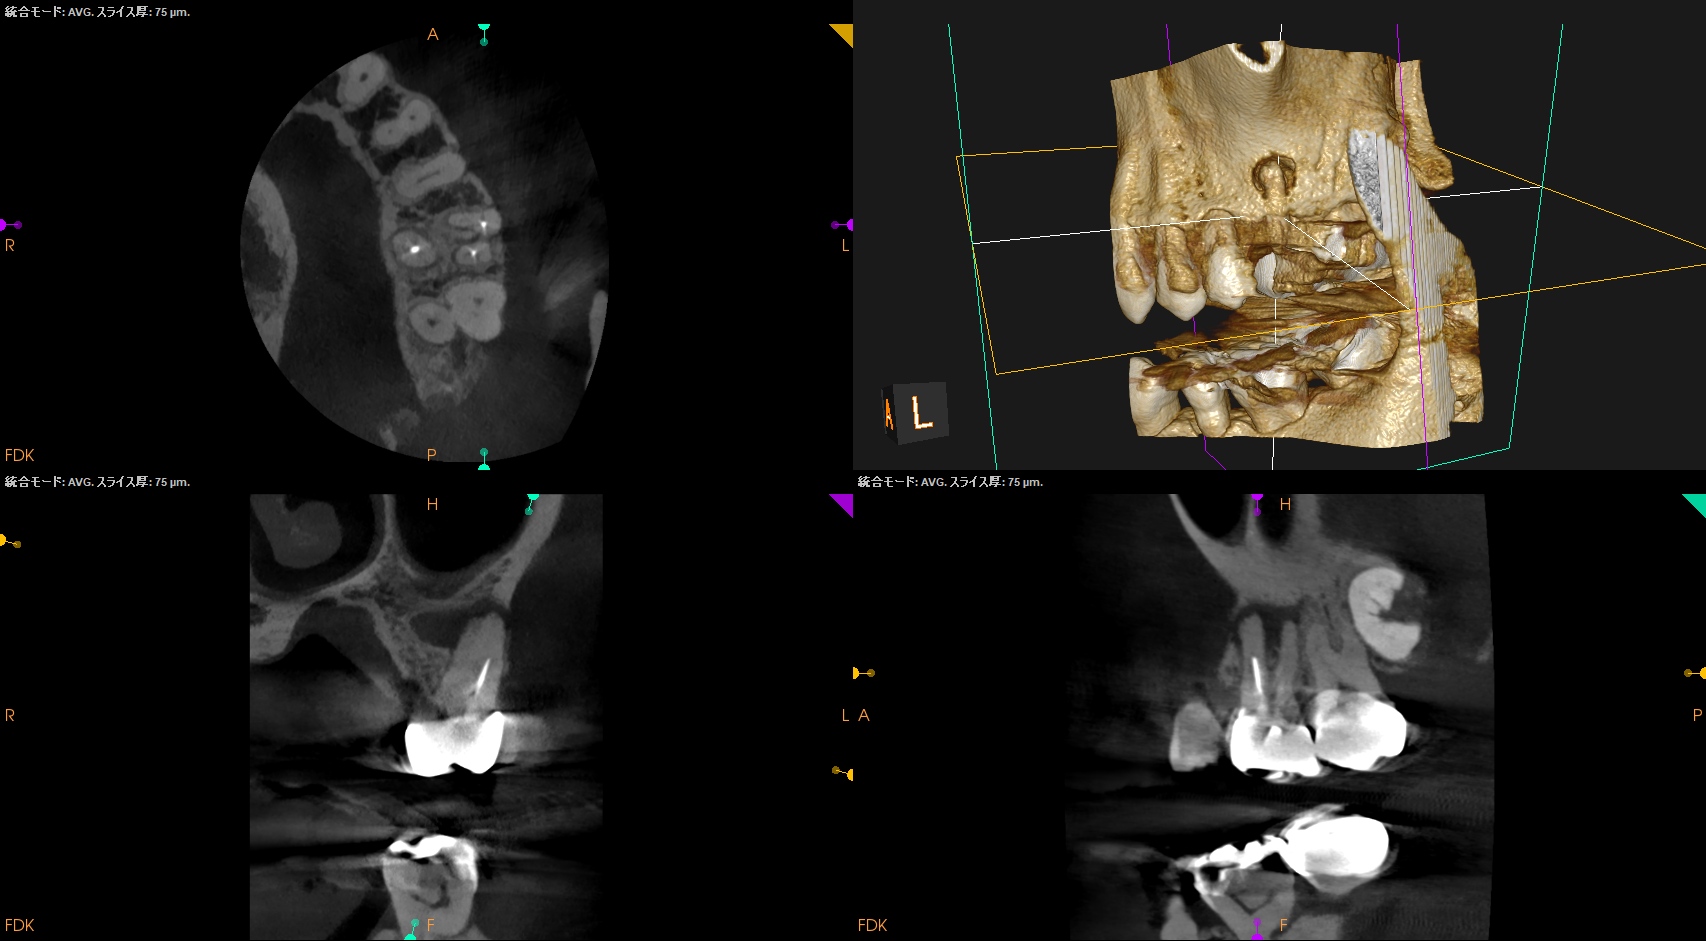

MB2を発見・穿通させる必要があるかどうか?はこのように術前にCBCTを正しく分析すれば予想ができる。

これが意味することは、

CBCTなくして、CBCTを分析できる能力無くして、歯内療法を制することができないと言うことがわかる。

MBは、

MBの作業長の予測は18~19mm(臨床的にはここからクラウンの厚み, この際はMB部分を引く必要性)ということがわかる。

DBは、

DBの作業長予測は17.4mm(ここからDBのクラウンの厚みを引いた長さ)

になろう。

が、正しくはRoot ZXが96%の可能性で正しい位置を提示してくれる。

そのためのガイドマップにCBCTは必須と言える。

Pre-op Endo Diagnosis(2026.1.28)

Pulp Dx: Previously treated

Periapical Dx: Symptomatic apical periodontitis

Recommended Tx: Re-RCT